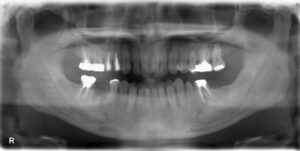

下顎1本欠損症例

BEFORE AFTER 51歳男性/下顎1本欠損/インプラント埋込手術 【治療内容】 右下第一大臼歯の欠損補綴について…